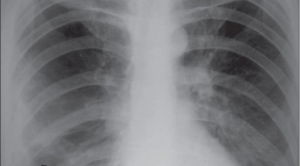

Ketentuan ciri pasien penyakit paru obstruktif kronis (PPOK) yang membutuhkan bulektomi sangat penting karena tidak semua pasien dapat/harus dilakukan bulektomi. PPOK merupakan...(Baca Selengkapnya)